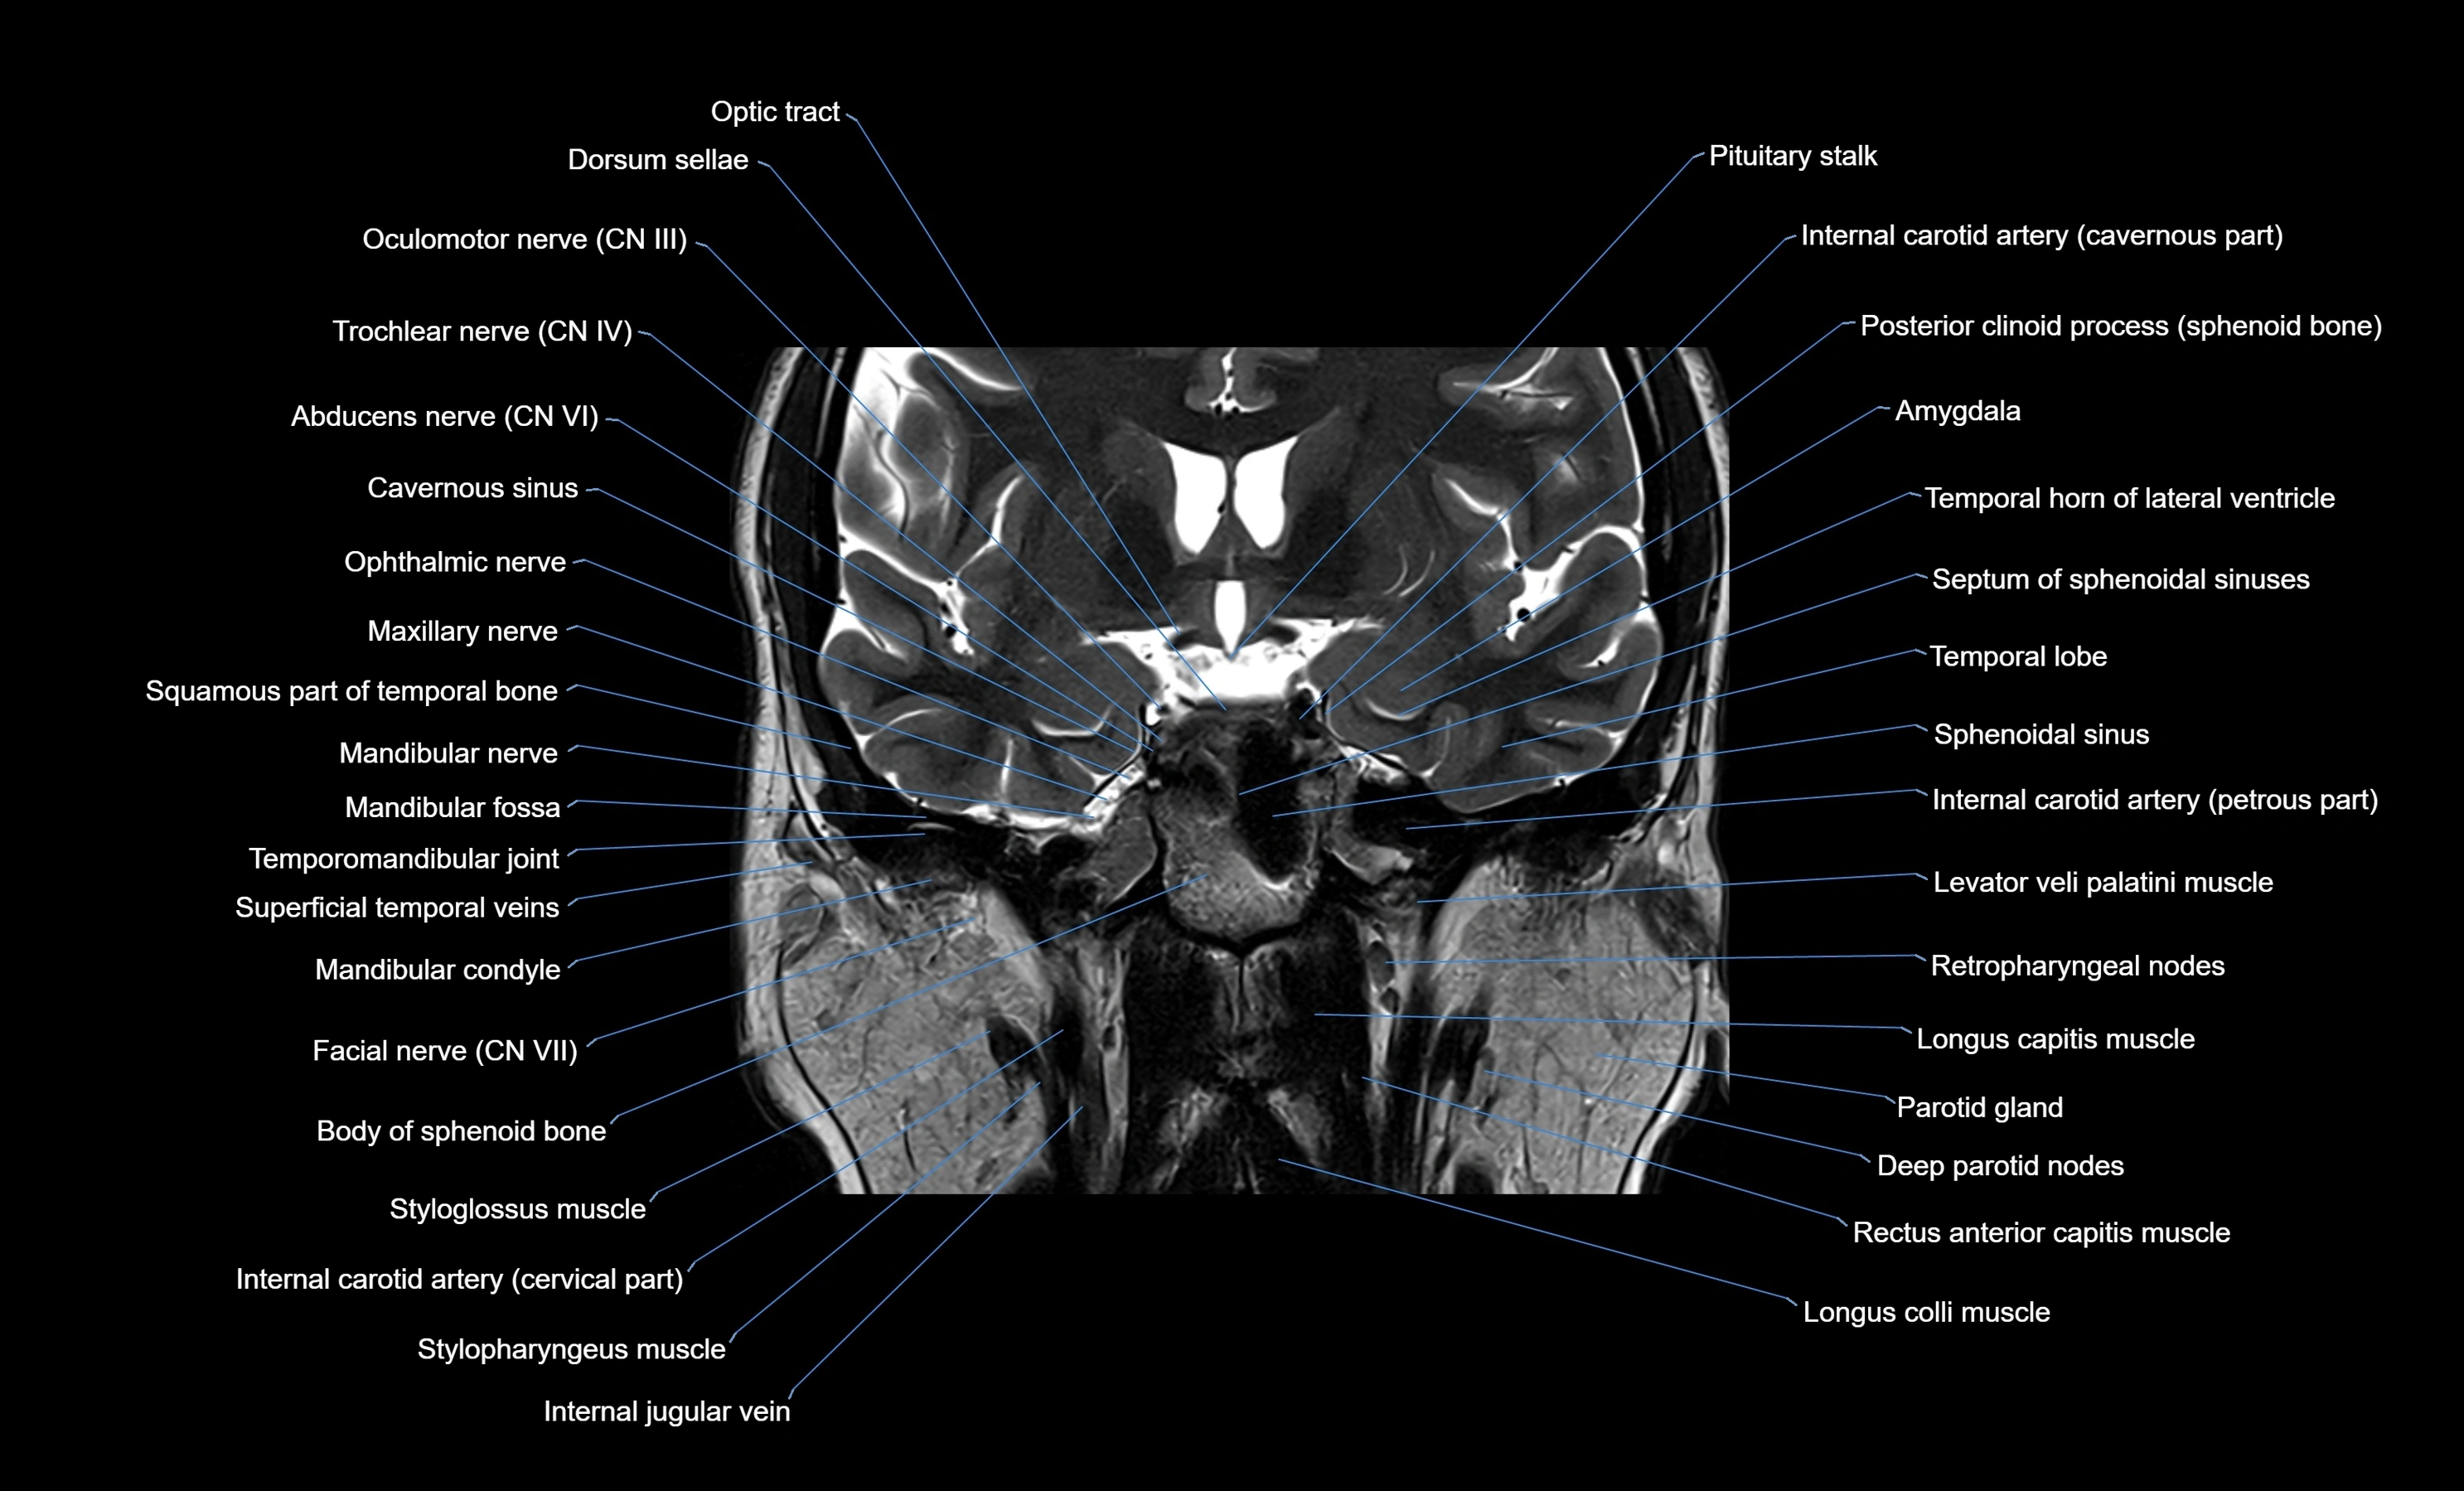

MRI images